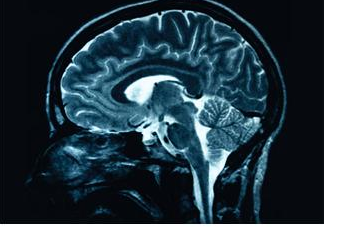

Earlier this month Brian Stann retired from his successful MMA career due to concerns regarding possible long term implications from traumatic brain injury.

Last week, Cole Harbour MMA fighter TJ Grant committed an equally impressive move in deference to head injury. He stepped down from his UFC lightweight title shot scheduled next month. This, despite not being guaranteed another shot at the title by UFC brass. The reason, a concussive injury sustained in practice with lingering post concussive issues.

In the personal injury world I’ve seen my share of post concussive issues and the lingering consequences these injuries can bring. Listening to TJ Grant’s interview with Ariel Helwani is worth digesting to in full to gain insight into the difficulties one can have recovering from a concussion and the minor exertions that can create significant setbacks.

As previously discussed, it is now well understood that combat athletes often sustain some of the worst trauma through training, not only by being exposed to possible concussions but through the accumulation of multiple sub concussive blows. TJ Grant should be commended not only for his personal sacrifice in the name of his health but for being an example to all combat sport participants that brain health should not be sacrificed for short term gain.